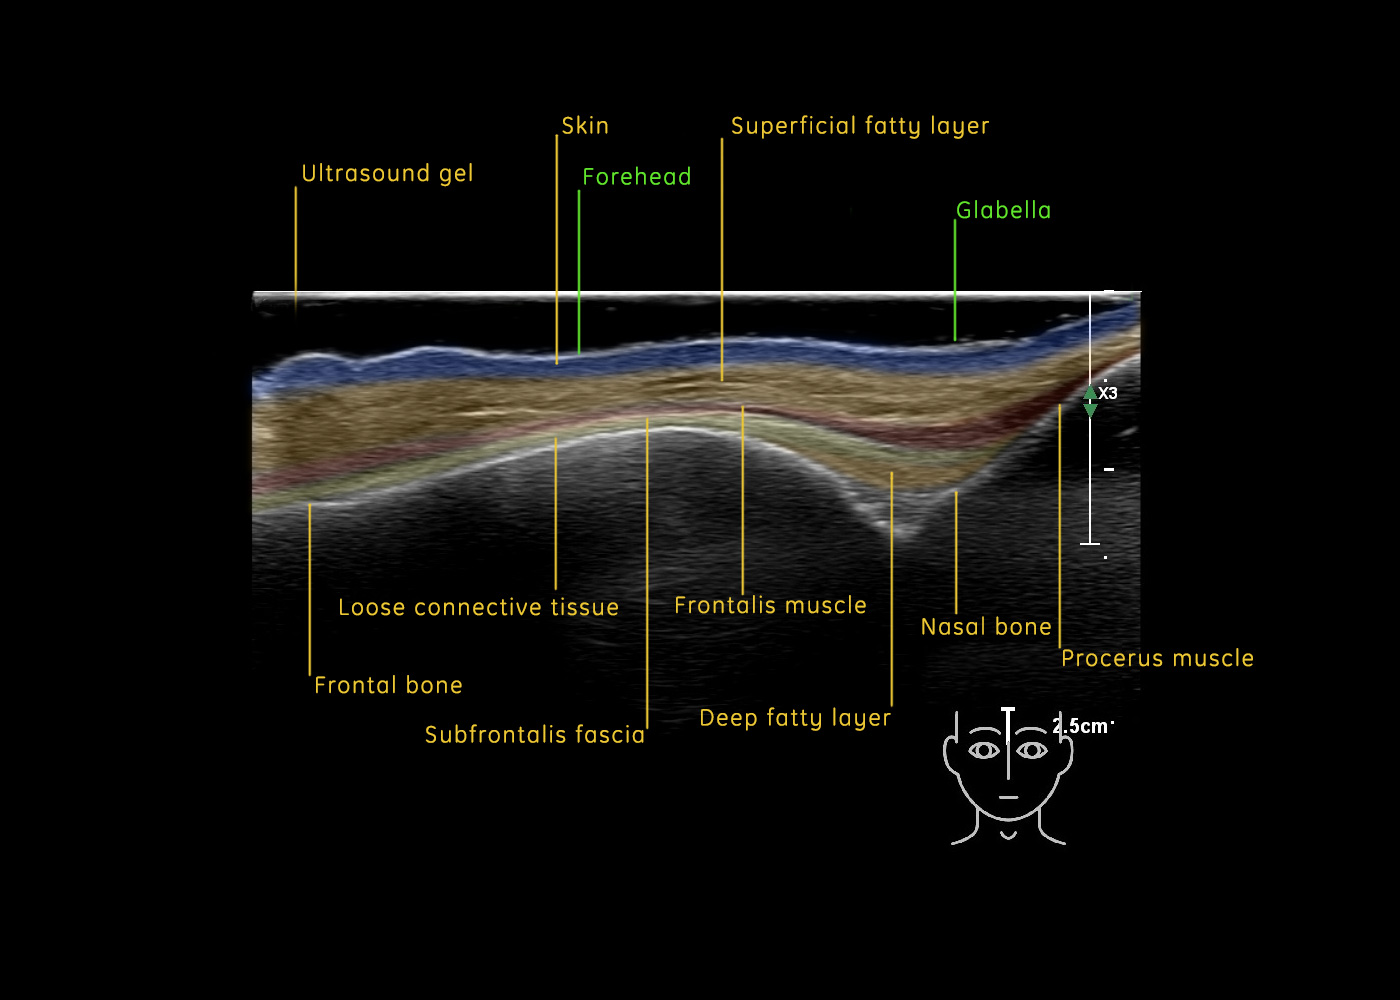

The forehead

In this section you will learn more about the different layers of the face with the use of ultrasound. When you click on the secondary ultrasound image, you will see the different structures as an overlay. This will help to train yourself to recognize the different layers of the face.

Study the first image to recognize the different layers. If you are sure about the layers, swipe to the second image to view the answer (if applicable).